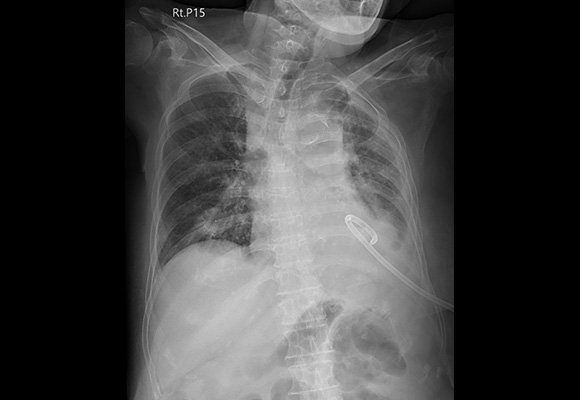

Endobronchial Ultrasound (EBUS)

The source highlights EBUS-guided FNAC and sampling of mediastinal nodes, work-up of extraluminal tumours and masses, and mediastinal staging of lung cancer, making this department relevant for both diagnostic pulmonology and oncologic thoracic pathways.